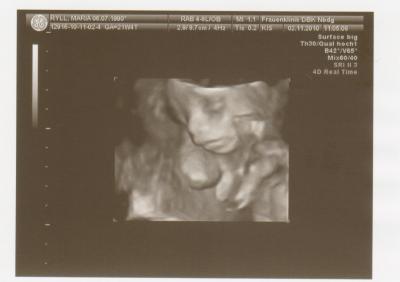

Hallo ihr Lieben, ich bin ganz begeistert Feinsono war echt toll! Es bleibt 100% beim Mädchen-Outing und es gab keine Auffälligkeiten!!! Sie sagte das es ein zierliches Mädchen ist, aber alle Werte sind im Normbereich. Aber mein Mann und ich sind ja auch weder groß noch kräftig gebaut. Sie ist jetzt 24,8cm groß und 367gr schwer. Der werdende Papa ist auch hin und weg. Hab ganz viele Bilder bekommen. Ein paar hänge ich euch mal an. liebe Grüße

Das 3-D-Bild ist super!!! Eine hübsche Maus wird das!